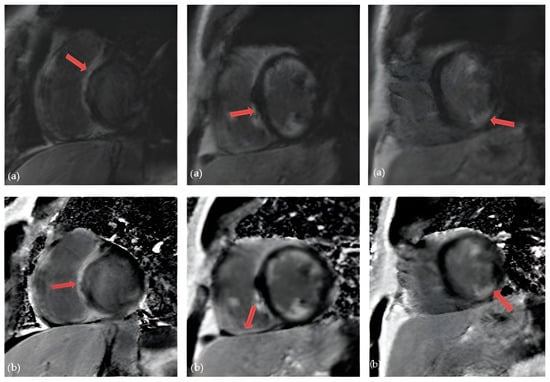

5.4. Cardiac Magnetic Resonance (CMR)

5.5. 18Fluorodeoxyglucose Positron Emission Tomography (FDG-PET)